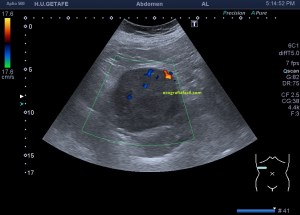

Con la eco pasa igual…cuando queremos estudiar, por ejemplo, el recto anterior del muslo en axial,perfecto…pero en longitudinal, como la imagen 2, se complica porque desde la rótula a la inserción en la cadera, tenemos mucho recorrido. En este caso hacemos lo mismo que cuando hacemos la foto del atardecer…nos ponemos en un extremo, activamos la funciona, recorremos suave y continuamente por la anatomía que queremos fotografiar y ya está…mira la pantalla y no el movimiento de tu mano,como si hicieses la foto, ves la pantalla,pero no como mueves el teléfono.

Es muy útil para lesiones que han crecido mucho y no podemos conjugar en una sola imagen, por ejemplo, un lipoma, cuando superan la medida de la huella de la sonda no son medibles, hay que usar «panoramic view», y como este caso, otros muchos.

Técnicamente es lo mismo, ambos dispositivos hacen una suma de imágenes que se plasman en un resultado final estupendo. Toda la escena más pequeña, pero más alargada que te da percepción de toda la magnitud de aquello que pretendes estudiar, te quita algo de detalle, pero te sirve para medir perfectamente y además puedes incrementar y mover la imagen con tu track ball…